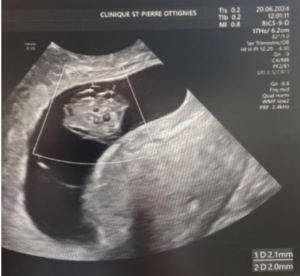

The ultrasound images demonstrated a single spinal column, two stomachs, and two hearts (Figure 2A). Two fused abdomens were observed, along with subcutaneous edema measuring 2.0 mm and 2.1 mm (Figure 2B). In addition, two pairs of moving legs were identified (Figure 2C). The trophoblast was located anteriorly, and a single corpus luteum was observed in the left ovary. Two follow-up examinations were required at 9 and 10 weeks of gestation to establish the diagnosis. At 9 weeks of gestation, the 3D ultrasound images lacked sufficient clarity for a definitive diagnosis (Figure 3). At 10 weeks of gestation, color Doppler imaging demonstrated two distinct cardiac activities, indicating the presence of two separate circulatory systems (Figure 4A). Three-dimensional imaging further revealed the face of one of the conjoined twins and confirmed the presence of two umbilical cords (Figure 4B).